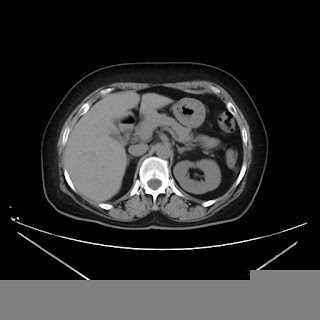

A CT abdomen revealed a left adrenal cortical tumor.

CT images: